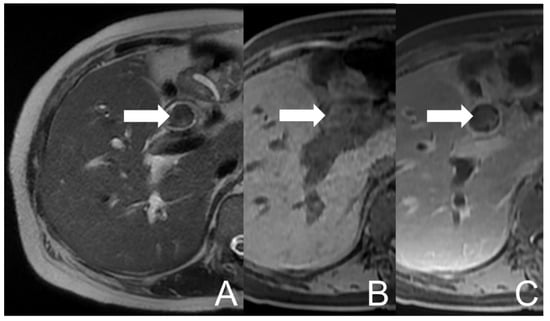

She suffered from abdominal pain in the right upper quadrant along with right flank and back discomfort for 2–3 months. The symptoms exacerbated and she went to a local hospital where abdominal computed tomography (CT) revealed dilatation over IHD and CBD in the presence of stones. Acute cholangitis was impressed and antibiotics were prescribed. The symptoms of fatigue, poor appetite, jaundice, low-grade fever and right epigastric pain developed again in spite of therapy. She visited our Emergency Department for medical help, where cholangitis was suspected. She was subsequently admitted for further evaluation and management. Endoscopic retrograde cholangiopancreatography (ERCP) was performed which showed hemobilia in the presence of lots of tissue material and blood clots within CBD. Some tissue material was extracted and sent to pathologic examination. Magnetic resonance cholangiopancreatography (MRCP) was arranged, which revealed dilatation and mild increase in wall thickness and enhancement of the biliary tract. A lobulated lesion in CHD and CBD was also found, extending to the confluence (about 9.8 cm × 1.9 cm), with heterogeneous signal intensities on the T1-weighted image (mainly high signal intensity) and T2-weighted image (mainly low signal intensity). Some equivocal enhancing foci of the lesion were suspected (Figure 1). The impression of cholangitis could be compatible, accompanied with possible debris, hematoma or neoplasm. The pathology reported an admixture of blood clots, fibrin and inflammatory cells. Aggregation of histiocytes and scanty pancreatobiliary-type epithelium with bland cytologic features was noted whilst there was no evidence of malignancy. A blood culture yielded Escherichia coli. Empirical antibiotics were prescribed and the symptoms subsided. The patient was discharged under a stable condition.

Figure 1. UCOGC of CHD and CBD in a 66-year-old female. The initial axial MRI images show a mass (arrow) with heterogeneous signal intensities in CBD, demonstrating relatively low signal intensity on the T2-weighted image (A) and relatively high signal intensity on the pre-contrast T1-weighted fat-saturated image (B), with faint enhancing foci on the post-contrast T1-weighted fat-saturated image (C). The imaging findings are suggestive of a neogrowth with hemorrhage.